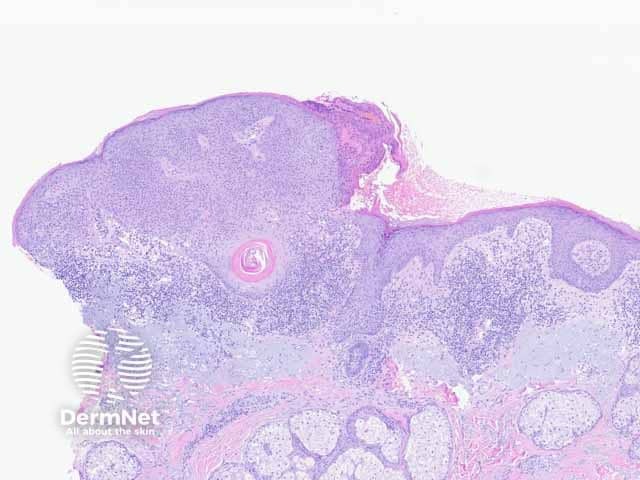

Seborrhoeic keratosis is a well-demarcated exophytic, flat or, less commonly, endophytic lesion composed of a proliferation of epidermal keratinocytes. Seborrhoeic keratosis can be recognised by a papillomatous architecture, acanthosis, hyperkeratosis, and horn cysts. The hyperkeratosis produces a characteristic loose lamellar stratum corneum. Squamous eddies may be present if particularly acanthotic.

Figure 1: regular acanthotic seborrhoeic keratosis